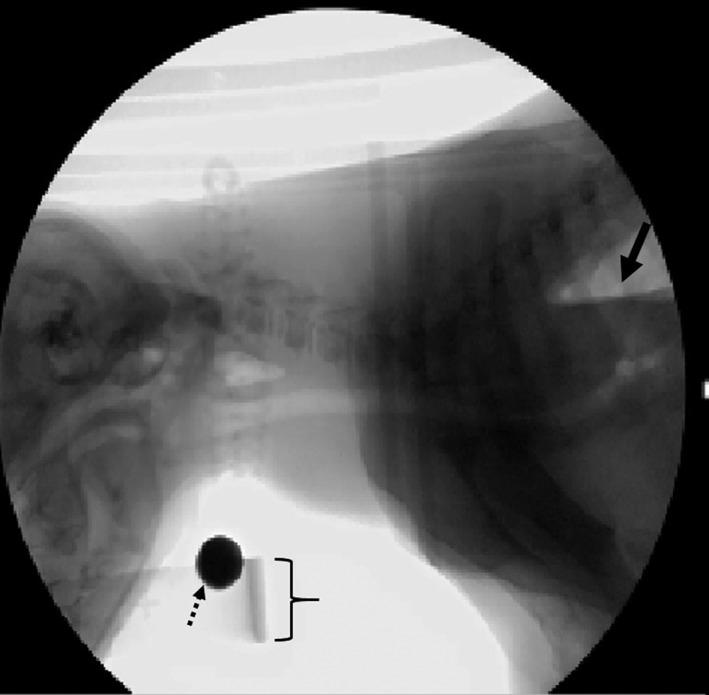

HYPOTHESIS/OBJECTIVES: To identify dogs with videofluoroscopic swallow study (VFSS) features of LES achalasia-like syndrome (LES-AS). We hypothesized that dogs with LES-AS could be distinguished from normal dogs using standardized VFSS criteria.

Retrospective study. One-hundred thirty dogs presented to the University of Missouri Veterinary Health Center (MU-VHC) between April 2015 and December 2017 for a free-feeding VFSS; 20 healthy dogs were included as controls. Swallow studies were evaluated for failure of the LES to relax during pharyngeal swallow (LES-AS). Affected dogs subsequently were evaluated using standardized criteria to identify metrics important for identifying and characterizing dogs with LES-AS.

Nineteen dogs with LES-AS were identified out of 130 VFSS. Megaesophagus was present in 14 of 19 (73.7%) dogs with LES-AS. A baseline esophageal fluid-line and "bird beak" were present in 68.4% (95% confidence interval [CI], 47.5%-89.3%) and 63.2% (95% CI, 41.5%-84.8%) of affected dogs, respectively. The esophagus was graded as acontractile (8/19), hypomotile (8/19), or hypermotile (3/19).

Dogs with LES-AS may successfully be identified by VFSS using a free-feeding protocol. These data are of critical clinical importance because a subpopulation of dogs with functional LES obstruction may be candidates for targeted intervention.

假设/目的:确定具有 LES 失弛缓症样综合征(LES-AS)的食管造影吞咽研究(VFSS)特征的犬。我们假设可以使用标准化的 VFSS 标准将具有 LES-AS 的犬与正常犬区分开来。

回顾性研究。2015 年 4 月至 2017 年 12 月,130 只犬在密苏里大学兽医学院就诊(MU-VHC)进行自由喂养 VFSS;20 只健康犬作为对照。吞咽研究评估 LES 在咽部吞咽期间是否无法放松(LES-AS)。受影响的犬随后使用标准化标准进行评估,以确定识别和表征 LES-AS 犬的重要指标。

在 130 次 VFSS 中确定了 19 只具有 LES-AS 的犬。19 只 LES-AS 犬中有 14 只(73.7%)患有巨食管。68.4%(95%置信区间[CI],47.5%-89.3%)和 63.2%(95% CI,41.5%-84.8%)的受影响犬存在基线食管液体线和“鸟嘴”。食管被分级为无收缩(8/19)、低动力(8/19)或高动力(3/19)。

LES-AS 犬可通过使用自由喂养方案的 VFSS 成功识别。这些数据具有重要的临床意义,因为功能性 LES 阻塞的犬亚群可能是靶向干预的候选者。